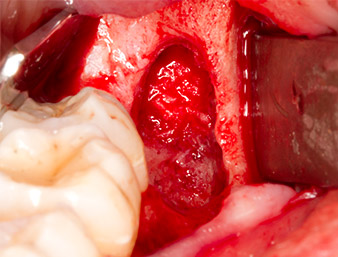

Le tissu recouvrant le reste radiculaire n’est pas entièrement ossifié et est essentiellement constitué de tissu de granulation modifié par l'inflammation (Fig. 4).

Tissu de granulation

Fig. 4 : Deux écarteurs Lagenbeck et un raspatoire exposent la zone d’intervention. On aperçoit le tissu de granulation de la première ostéotomie non totalement cicatrisée.